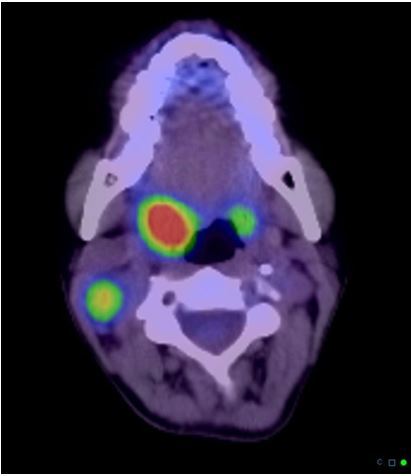

16

Q

-imaging modality -orientation -body part -abnormality

A

-PET-CT fused image -axial -neck -bilateral squamous cellw carcinoma of the tonsils with nodal metastasis